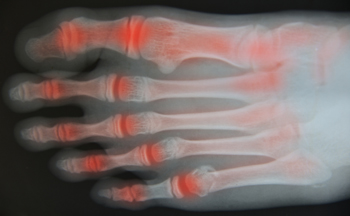

Aging can affect the way the feet feel and move, and seniors often notice changes in balance, comfort, and stability as soft tissues lose elasticity and arches weaken. Joint stiffness, bunions, stress fractures, and changes in bone strength can make walking uncomfortable. This is especially true when shoes that lack adequate support or worn-down flip-flops place extra pressure on the toes and heels. Seniors are also more prone to conditions like plantar fasciitis and Achilles tendinitis as the arches flatten and the ligaments stretch. Regular foot checks help identify swelling, changes in toe alignment, and areas of irritation before they worsen. A podiatrist can assess gait, evaluate the health of the toes, ankles, and arches, and recommend treatment to protect long-term mobility and keep the feet functioning well. If you are an older adult experiencing foot problems, it is suggested that you make an appointment with a podiatrist for a diagnosis and treatment.

When people age, some common issues that may occur are bone density loss, dry skin, poor circulation, and rough brittle nails. These issues may also affect your foot health if the necessary steps are not taken to alleviate the problems.